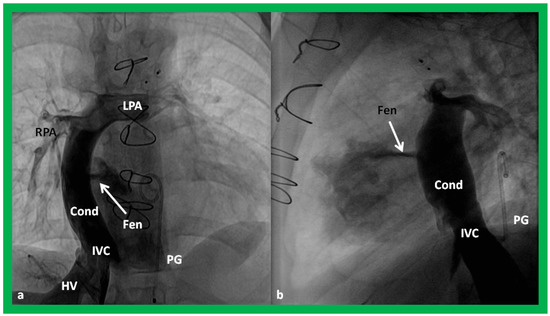

Surgically created fenestrations (Figure 50, Figure 51, Figure 52 and Figure 53) can also be demonstrated by color Doppler studies and the mean gradient across the fenestration (Figure 52 and Figure 53) is helpful in determining the physiologic state; a mean gradient of 4 to 8 mmHg is considered adequate.

Angiographic counter part of the Fontan conduit with fenestration is shown, in Figure 54, to have better comprehension of the anatomy of the Fontan.

Article Metrics

Back to TopTop